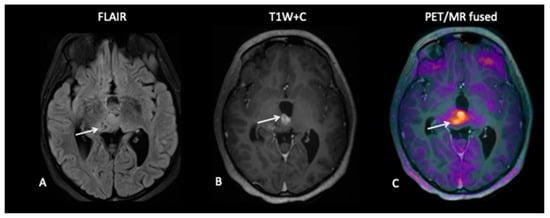

A 10-year-old presented with low-grade glioma with a background of NF1 (neurofibromatosis type 1). A mid treatment MRI scan following disease progression showed enlargement of an enhancing lesion in the right cerebellar hemisphere, but the patient was well and clinically stable, and the radiological changes were thought to reflect pseudoprogression. An FDOPA PET–MRI showed increased tracer activity in the enhancing lesion along with a second FDOPA avid lesion in the right subthalamic region, consistent with metabolically active disease (Figure 9).

Figure 9.

A mid-treatment scan demonstrates an enlarging right cerebellar hemisphere lesion (A,B) thought to reflect pseudoprogression, but FDOPA demonstrates increased uptake (C) and identifies a further lesion in the midbrain (F) not obviously apparent on the T2W image (D) or T1W post-contrast image (E), which is consistent with multifocal tumour progression.